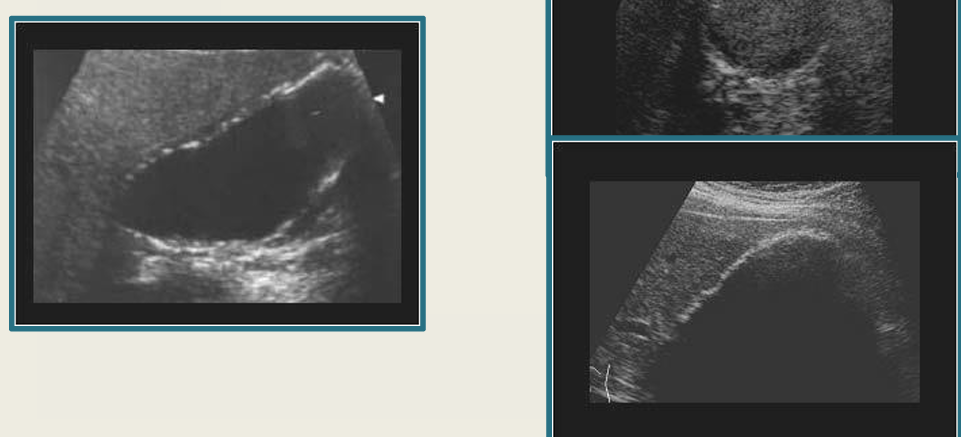

term image

GB polyps

chronic cholecystitis

Mirizzi syndrome